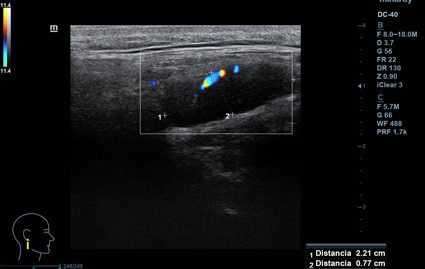

Lesión hipoecogénica cervical de aspecto sólido, de 2,5 x 1 cm (ancho x alto), con hilio vascular que preserva, impresiona de residual, vascularizado (Doppler). Otras lesiones similares de menor tamaño, pero con hilio mejor preservado, de aspecto benigno. Todas las lesiones impresionan de adenopatías. A nivel contralateral: lesiones similares en menor cuantía, también de aspecto benigno. Tiroides normal.